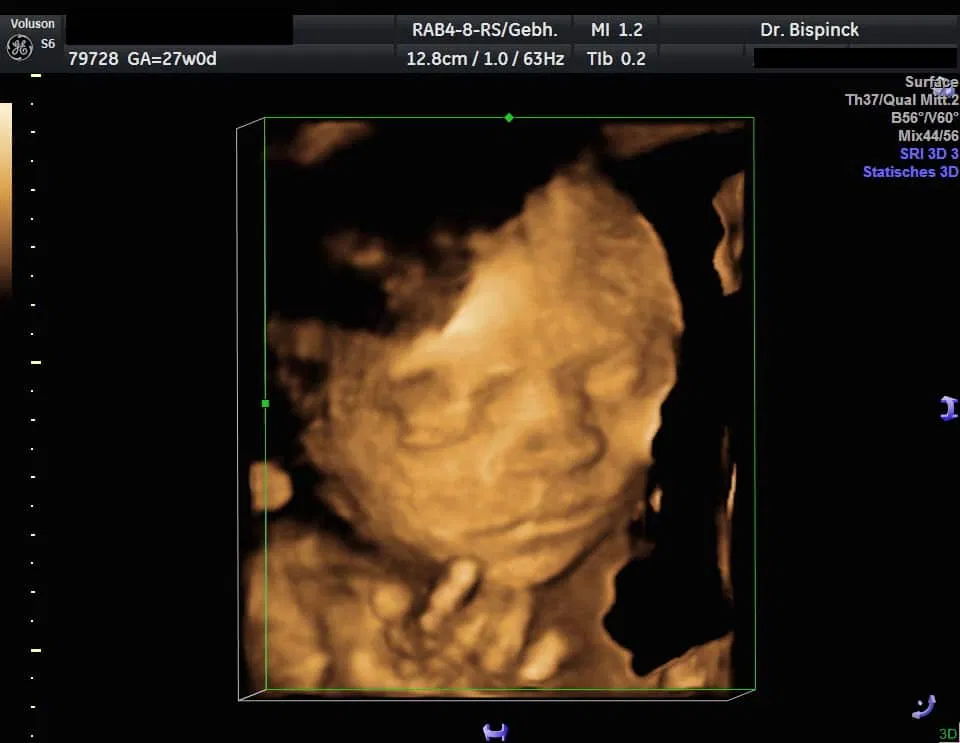

3D/4D Ultraschall

Gerne geben wir Ihnen Bildausdrucke mit.